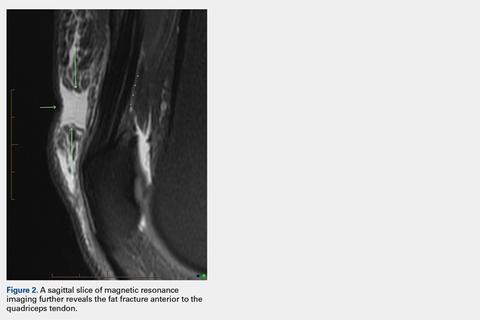

An acutely marginated, 1.5 cm × 3 cm, longitudinal and transverse fluid defect “crevasse” was identified at the midline in the prepatellar subcutaneous fat overlying the distal quadriceps tendon and corresponded to a clinically palpable abnormality (Figures 1, 2).

These findings were consistent with a localized “fat fracture.” There was an associated, 2 cm × 6 cm, sagittal and coronal/longitudinal, medial prepatellar bursal fluid complex and subcutaneous edema adjacent to the fat fracture (Figure 3). However, the patellar and quadriceps tendons were intact. A 12-mm focus of marrow edema at the superior pole of the patella was consistent with a contusion.